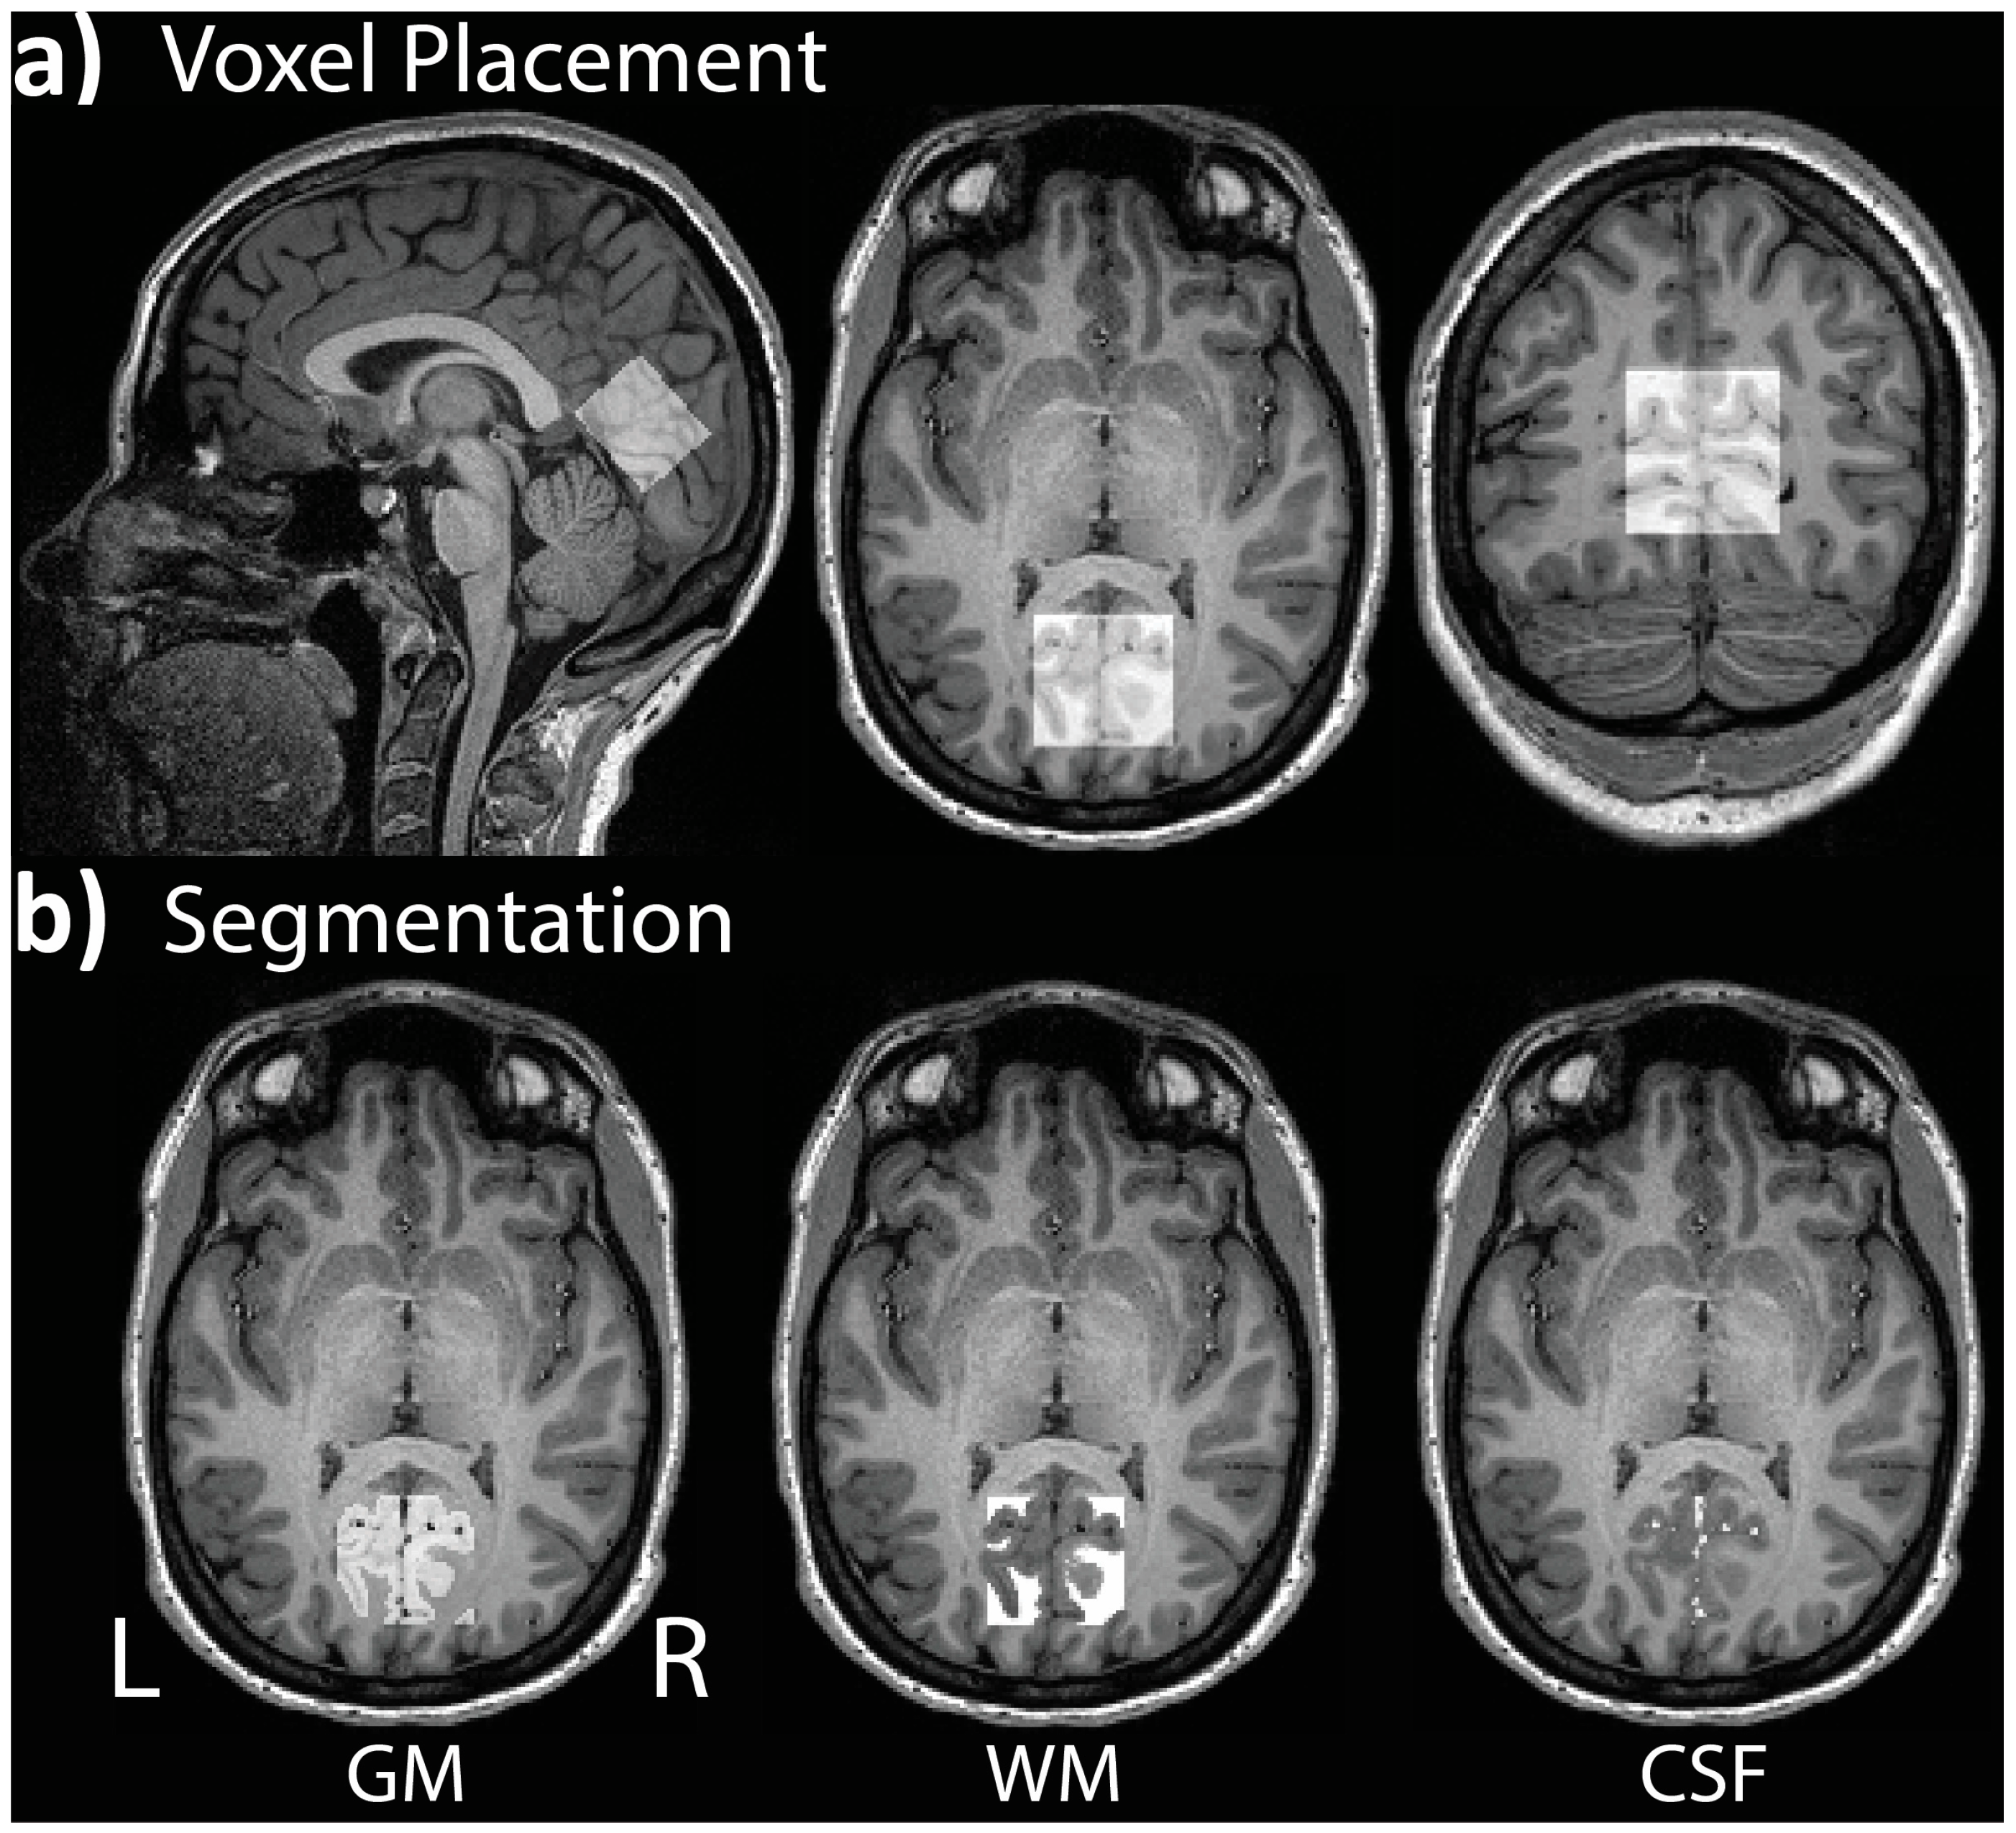

| VOI | PASC (n = 18) | CNT (n = 20) | F(1,36) | p |

|---|---|---|---|---|

| GM | 0.63 ± 0.05 | 0.62 ± 0.03 | 0.69 | 0.413 |

| WM | 0.29 ± 0.03 | 0.29 ± 0.03 | 0.84 | 0.366 |

| CSF | 0.09 ± 0.03 | 0.09 ± 0.02 | 0.10 | 0.760 |